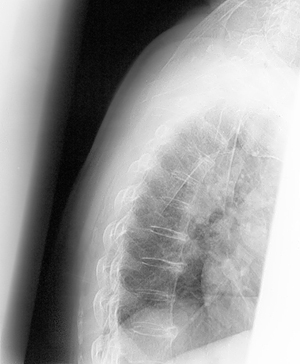

Continuing a popular but controversial treatment for osteoporosis could reduce spine fracture risk for a particular group of patients, but others could see little to no change if they discontinue it. Based on available evidence, a UCSF researcher reevaluated his 2006 finding from a randomized 10-year study of alendronate, a type of bisphosphonate – a class of drugs that prevent loss of bone mass.

Osteoporosis is responsible for 1.5 million fractures in the United States a year at a cost of $14 billion annually. As many as half of all women and a quarter of men older than 50 will break a bone due to osteoporosis, according to the National Institutes of Health.

The original study by Black and colleagues studied a total of 6,459 women for up to five years, comparing alendronate to a placebo. That study showed less fracture risk of spine, hip and other major bones and led to FDA approval of alendronate in 1997.

In a newer 2006 continuation study, 1,099 of the women who had taken alendronate for an average of five years at the start of the continuation study were randomly assigned to five more years of alendronate or a placebo. Those who continued on alendronate showed lower risk of spine fractures but no difference in risk for non-spine and hip fractures.